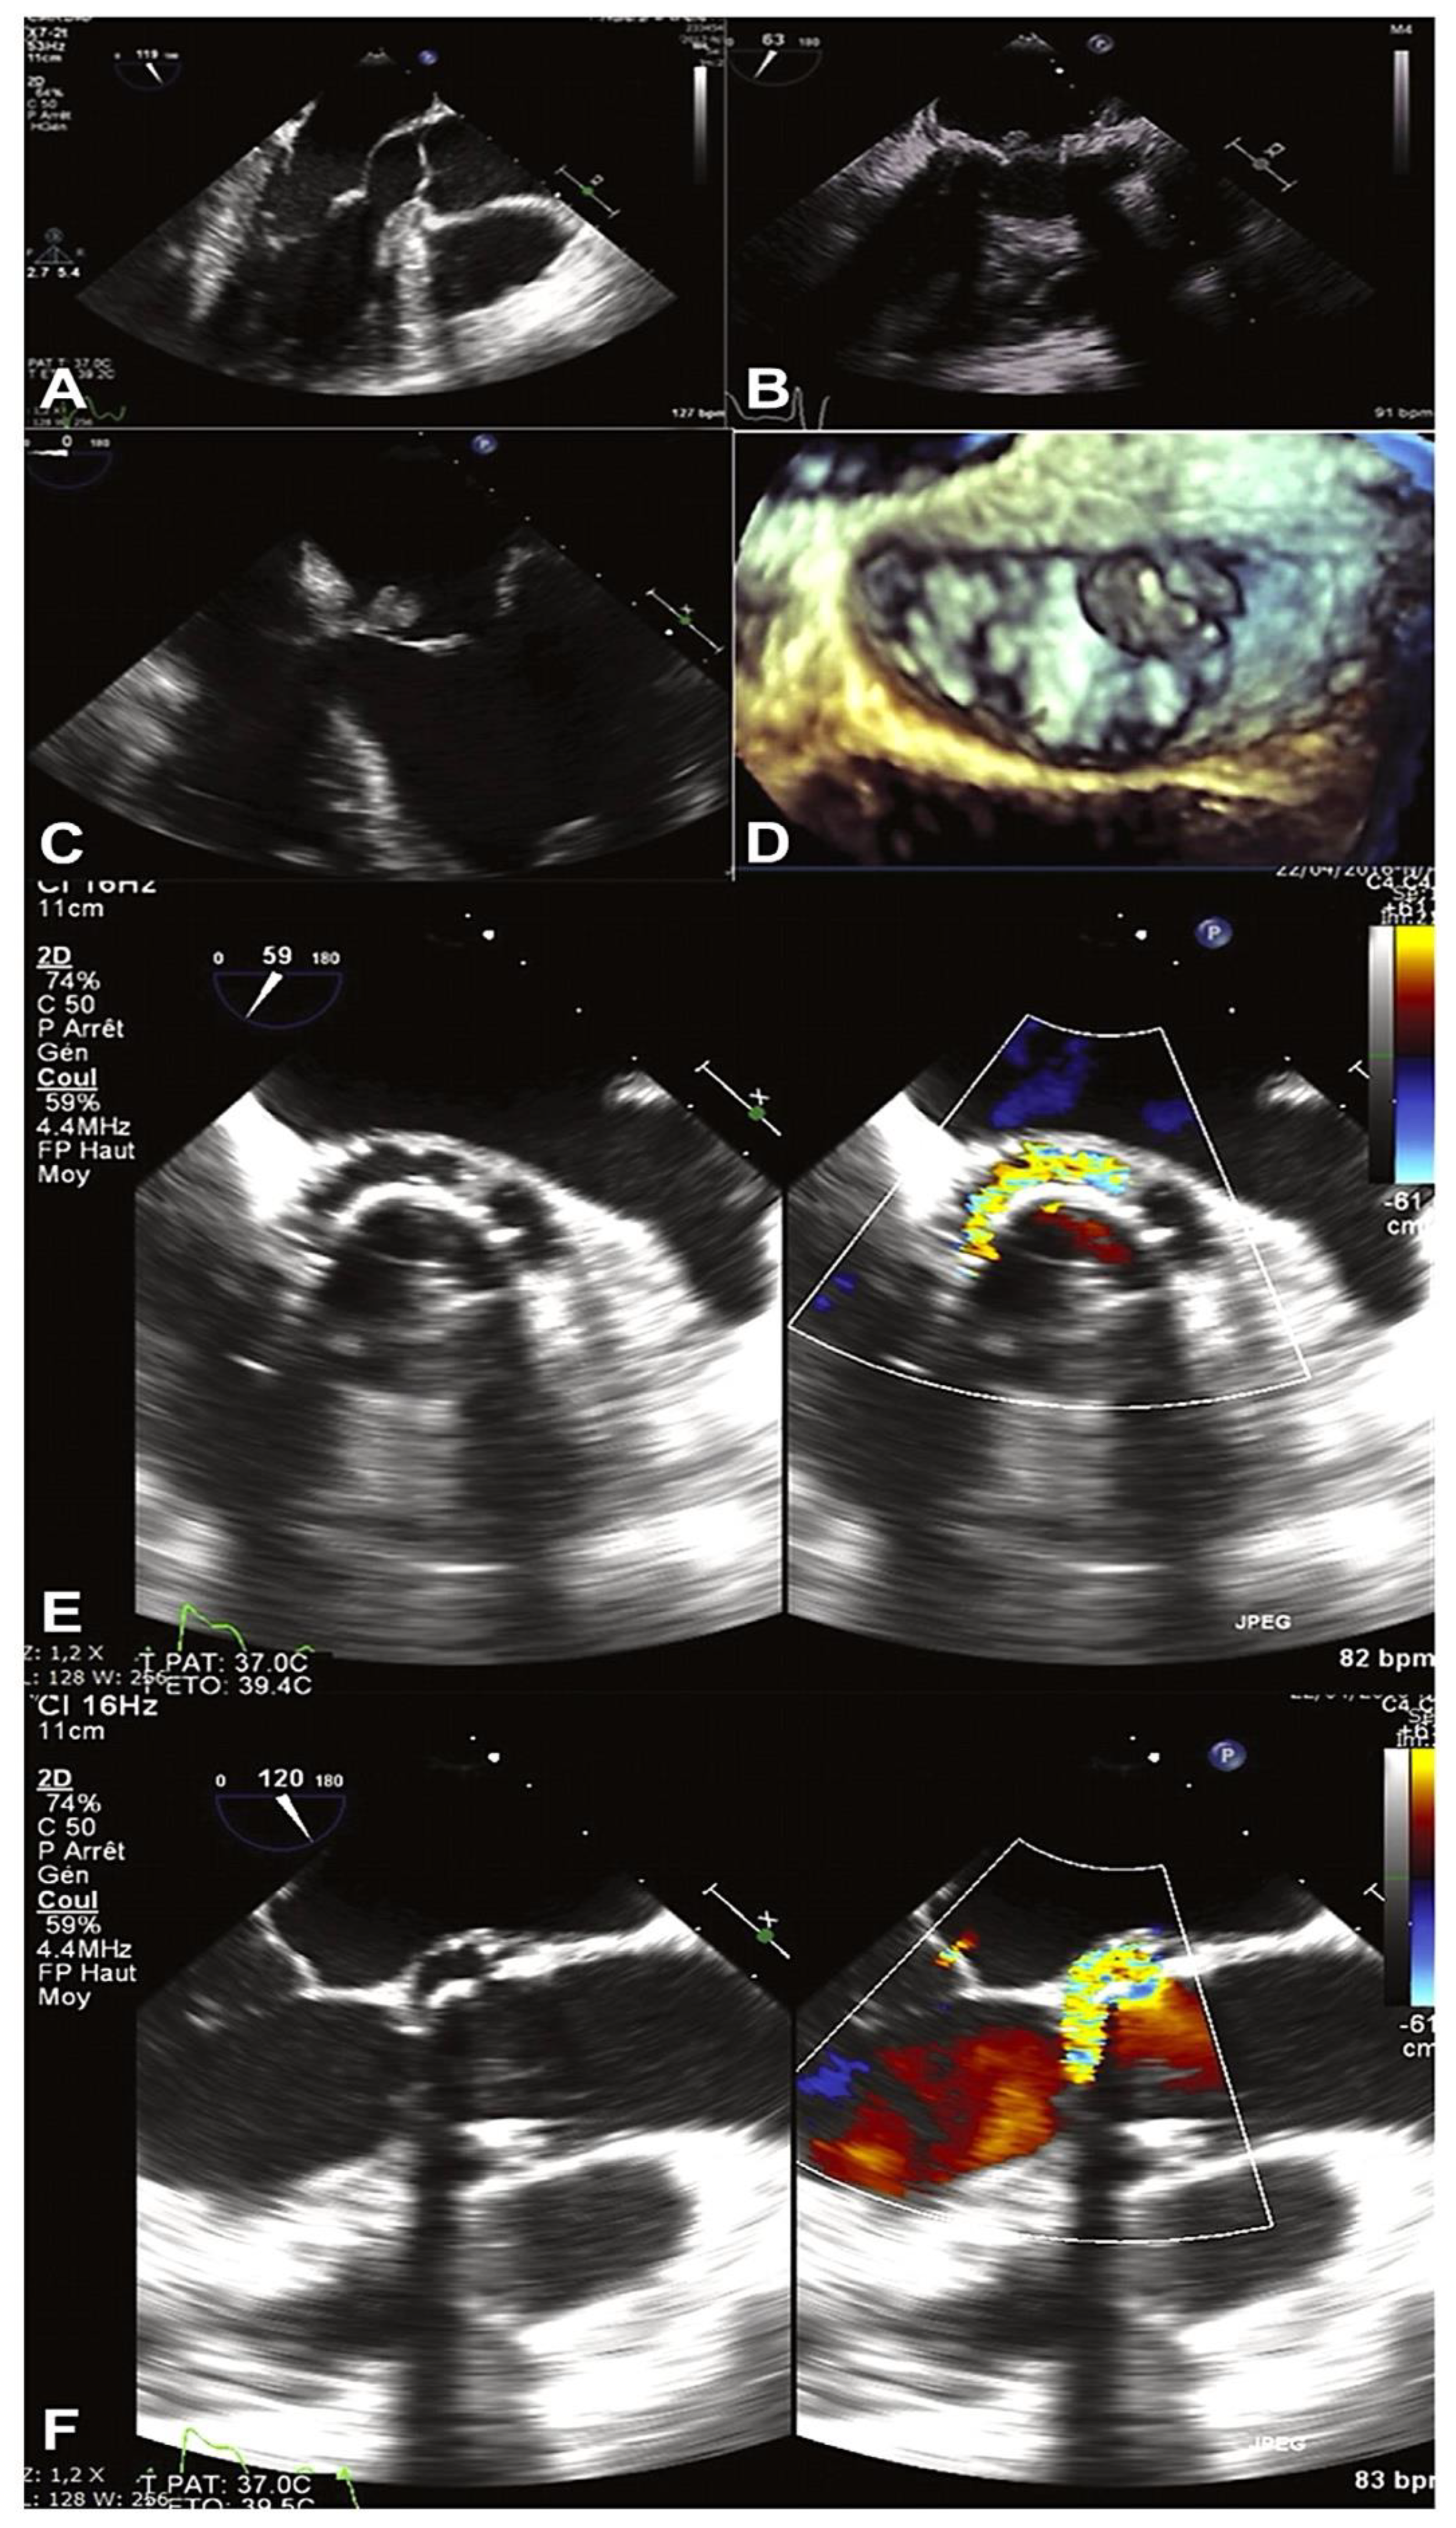

- Clinical Evidence: Imaging Criteria

- Mihos, C.G.; Nappi, F. A narrative review of echocardiography in infective endocarditis of the right heart. Ann. Transl. Med. 2020, 8, 1622. [Google Scholar] [CrossRef] [PubMed]

- Afonso, L.; Kottam, A.; Reddy, V.; Penumetcha, A. Echocardiography in infective endocarditis: state of the art. Curr Cardiol Rep 2017, 19, 127. [Google Scholar] [CrossRef]

- Avtaar Singh, S.S.; Costantino, M.F.; D'Addeo, G.; Cardinale, D.; Fiorilli, R.; Nappi, F. A narrative review of diagnosis of infective endocarditis-imaging methods and comparison. Ann Transl Med. 2020, 8, 1621. [Google Scholar] [CrossRef]

- Habib, G.; Badano, L.; Tribouilloy, C.; Vilacosta, I.; Zamorano, J.L.; Galderisi, M.; Voigt, J.U.; Sicari, R.; Cosyns, B.; Fox, K.; Aakhus, S.; European Association of Echocardiography. Recommendations for the practice of echocardiography in infective endocarditis. Eur J Echocardiogr 2010, 11, 202–219. [Google Scholar] [CrossRef] [PubMed]

- Bai, A.D.; Steinberg, M.; Showler, A.; Burry, L.; Bhatia, R.S.; Tomlinson, G.A.; Bell, C.M.; Morris, A.M. Diagnostic accuracy of transthoracic echocardiography for infective endocarditis findings using transesophageal echocardiography as the reference standard: a meta-analysis. J Am Soc Echocardiogr 2017, 30, 639–646.e8. [Google Scholar] [CrossRef]

- De Castro, S.; Cartoni, D.; d’Amati, G.; Beni, S.; Yao, J.; Fiorell, M.; Gallo, P.; Fedele, F.; Pandian, N.G. Diagnostic accuracy of transthoracic and multiplane transesophageal echocardiography for valvular perforation in acute infective endocarditis: Correlation with anatomic findings. Clin. Infect. Dis. 2000, 30, 825–826. [Google Scholar] [CrossRef] [PubMed]